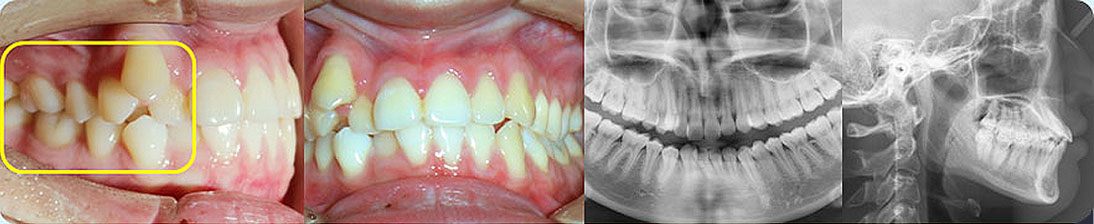

- 【診斷】

骨性Ⅱ類高角伴擁擠

上頜前突、下頜后縮、下前牙唇傾

下中線右偏2.5mm,21 35°扭轉(zhuǎn)13低位

打造醫(yī)生:德倫口腔正畸中心熊小琴主任

- 【治療方案】

拔除3顆多余的咬合不正的智齒,通過(guò)支抗釘控制

失狀向和垂直向,推上、下牙遠(yuǎn)移解決擁擠改善前

突,使整個(gè)頜平面逆時(shí)針旋轉(zhuǎn),改善了下頜后縮的

情況

矯治前后對(duì)比

牙列整平排齊,前牙內(nèi)收;覆蓋、覆合正常;尖牙和磨牙達(dá)到中性關(guān)系;上下中線對(duì)齊;下頜后縮改善